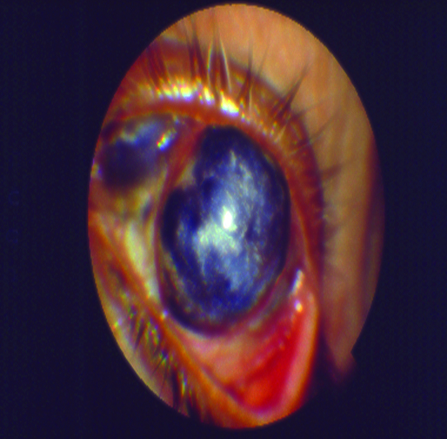

El tratamiento quirúrgico se enfoca específicamente en la reparación del posible daño severo que el ojo seco y generalmente sus patologías sistémicas asociadas pudieran haber provocado sobre la superficie ocular (Fig. 19).

Figura 19: Daño severo de la superficie ocular

Dentro del tratamiento quirúrgico se encuentran los injertos de limbo, los injertos de amnios y las queratoplastias.